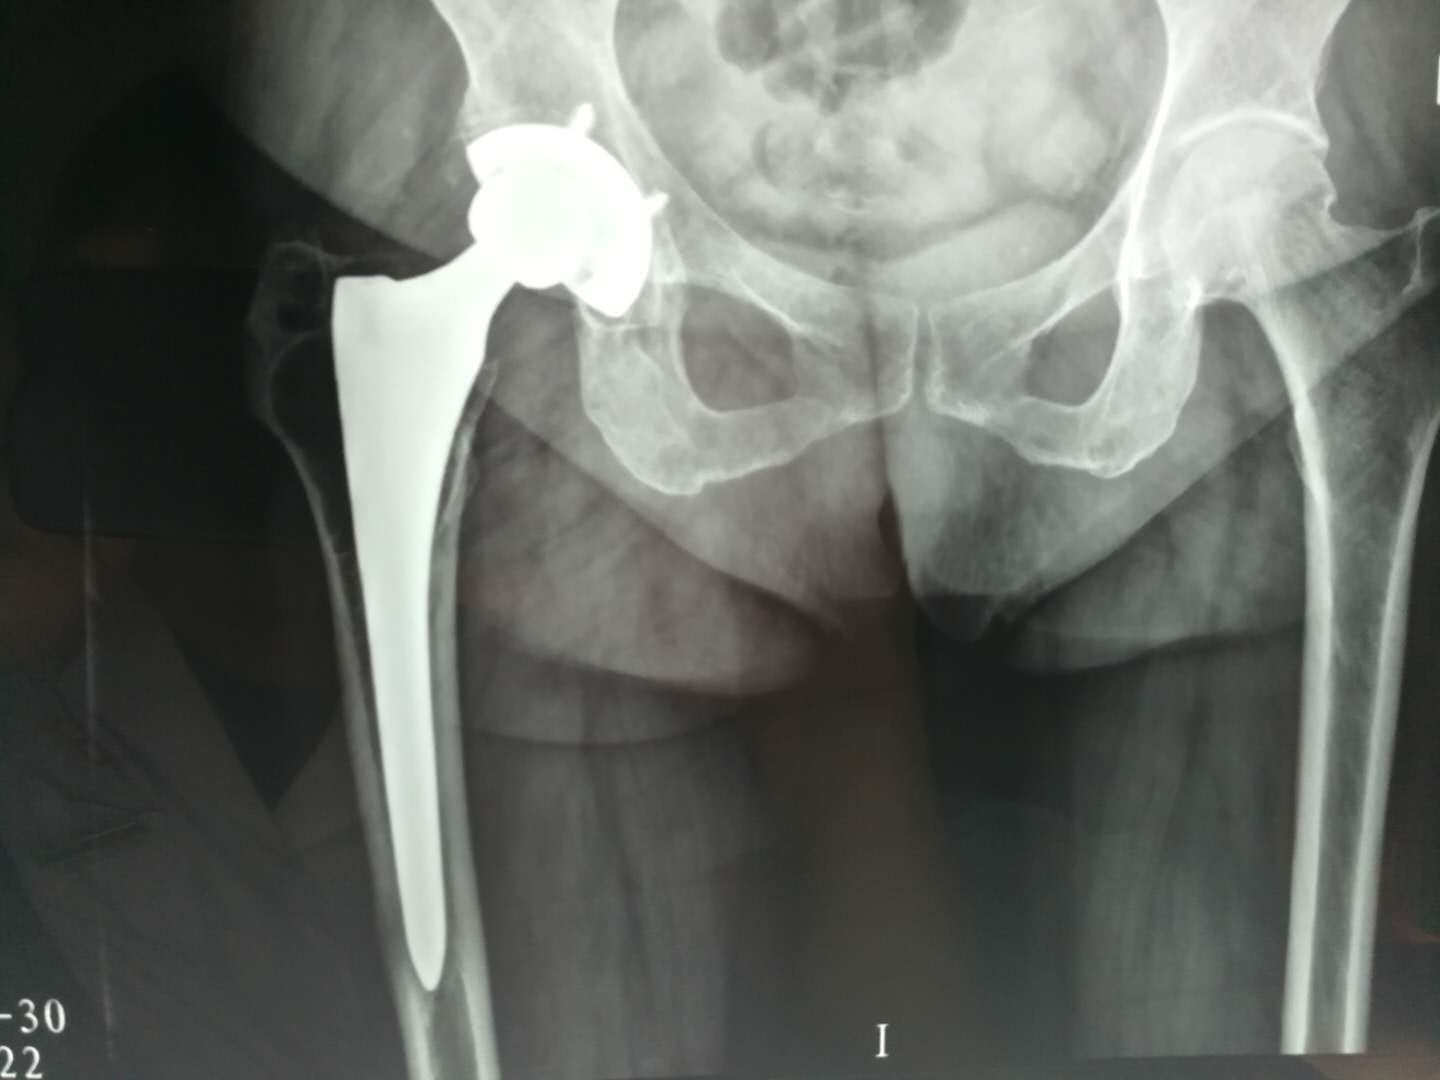

股骨头坏死分期的I、II、III期患者可以进行保髋治疗:包括减轻负重、高压氧治疗、脉冲电刺激治疗、高频冲击波治疗、药物治疗、保髋手术:髓芯减压、髓芯减压+干细胞移植、带血管蒂骨瓣移植术(带旋髂浅动脉髂骨瓣、带旋股外动脉横支大粗隆骨瓣)、粗隆间或股骨基底旋转截骨,IV、V期患者只能进行人工全髋关节置换手术治疗。

6.股骨头坏死到了什么程度必须换关节?

从X片上发现自己的股骨头不圆了,并且出现疼痛,这时可能要考虑换关节。而针对一些X片上显示股骨头不圆,却没有感到疼痛的患者,同时没有出现髋关节活动受限时可以暂时不换关节。换言之,只有当股骨头坏死导致出现骨关节炎,一活动就疼,影响到日常生活时,才需要做髋关节置换。

7.股骨头坏死患者做关节置换的最佳时机?

股骨头缺血性坏死的患者多为中青年,很多患者担心过早进行关节置换可能存在假体使用寿命的问题,但随着材料学的进步和手术技术的发展,目前的四代陶瓷对陶瓷界面全髋关节置换术后30年的假体生产率已经超过90%。同时人工关节没有自我更新及修复的能力,因此应该有“定期保养”的意识,但这种“保养”并不需要手术或吃药,只要患者每年拍摄一次髋关节的X光片,手术医生通过与术后即刻的X光对比就可以明确是否存在磨损及磨损的程度。在出现磨损征象的早期,只要通过简单的更换人工髋关节的衬垫就等于更换了一套全新的假体,不需要进行大翻修手术。

因此只要患者出现股骨头塌陷、关节疼痛症状影响生活或髋关节功能受限时就应该考虑进行进行人工全髋关节置换手术,尽快恢复正常生活,提高生活质量,保护髋关节功能。